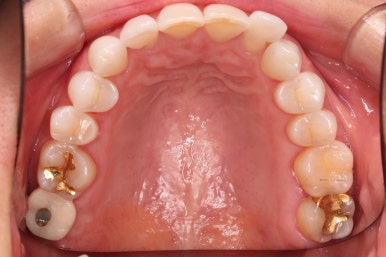

초진 시 입안의 모습입니다.

환자분이 원하셨던 부분은 윗니 작은 앞니가 하나 튀어나와서 개선하고 싶어하셨습니다.

부가적으로 아랫니 앞니가 마모가 심하여 높낮이가 달라보이는 점이었는데요.

윗니에만 장치를 부착하고 부분교정을 시작했습니다.

환자분이 연산동부분교정 선택하신 장치는 엠파워 클리어라고 하는 자가결찰 세라믹 장치입니다.

장치 부착한 모습 참고해 주시고요.